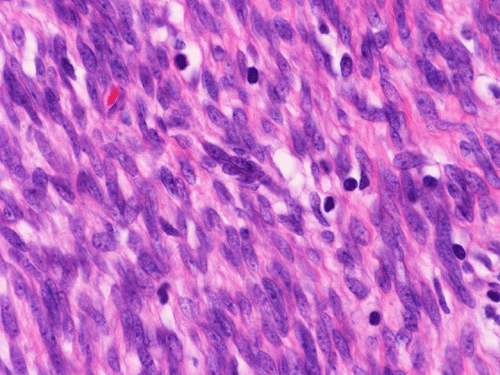

The excised mass is composed of an intermingled arrangement of mature adipose tissue, densely packed primitive spindle cells with small amount of cytoplasm, and mature appearing spindle cells with substantial amount of cytoplasm that gives the appearance of smooth muscle (Panel  A). Abrupt transition between the three elements are common (Panel B). The densely packed, small primitive spindle cells have elongated, cigar-shaped nuclei with amphophilic cytoplasm. Pleomorphism and mitotic figures are not seen. A small number of lymphocytes are present among these cells (Panel C). In areas with appeance of smooth muscle, the cells have elongated, sometime wavy nuclei without significant pleomorphism or mitosis (Panel D). Areas with thick, wavy collagen fibers admixed with benign appearing spindle cells are also present (Panel E and F) and some of these areas are more loosely packed than the other areas which may mimic the appearance of a neurofibroma. In contrast to other areas, these collagenous areas merge imperceptibly with the more cellular areas. In some of the densely packed spindle cell areas, there are small packets of loosely packed cells that give a myxomatous morphology on high magnification (Panel G and H).

Histologically, FHI has a triphasic organoid pattern with three distinct types of tissues: fibrous tissue; primitive mesenchyme appearing tissue; and mature adipose tissue. The fibrous tissue consists of well-differentiated spindle cells of fibroblastic/ myofibroblastic appearance admixed with a variable amount of collagen fibers. The dense fibrous tissue may form a fibrous core or at the center of the lesion. The primitive mesenchyme appearing tissue consists of sheets of undifferentiated spindle cells or stellate cells with an amphophilic and inconspicuous cytoplasm. Often these cells arrange in a concentric pattern and form whorls or characteristic ball-like structures in a vascular, mucoid matrix. Scattered lymphoid cells and extravasated erythrocytes are common findings in these areas.  The relative proportions of these three components vary in different cases greatly.